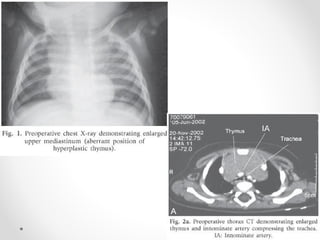

Relations of trachea in Superior

Mediastinum

• Anteriorly:

• Sternum

• Thymus

• Left brachiocephalic vein

• Origins of brachiocephalic

& left common carotid

arteries

• Arch of aorta

• Posteriorly:

• Esophagus

• Left recurrent laryngeal

nerve

Pleurae,  Trachea & Principal Bronchi By Dr Rabia Inam Gandapore.pptx

• Left side:

• Left common carotid & left

subclavian arteries,

• Left vagus & left phrenic

nerves

• Pleura

• Right side:

• Azygos vein

• Right vagus nerve